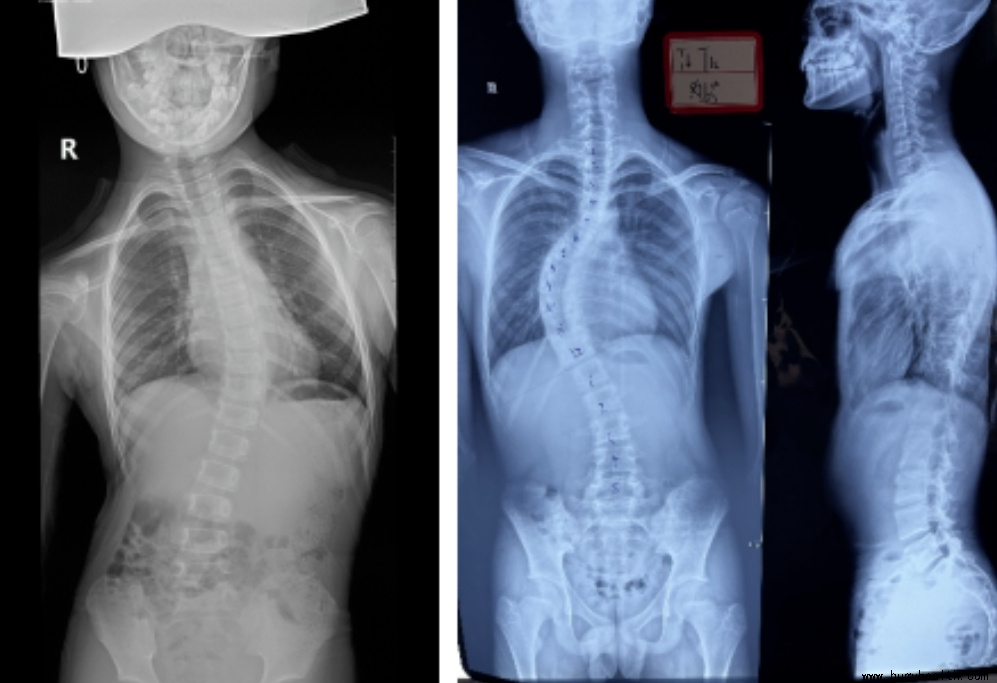

例子一:这是一个12岁的孩子,平时住校,当我们看到第一张图的时候好像没有什么问题,当脱去外套的时候,只是发现两边肩膀不一样高,好像也没有什么大问题,但是当她弯腰的时候就很明显看出脊柱两边的肌肉不一样高,就是剃刀背已经很明显了,最后我们再来看看拍出来的片子,孩子的侧弯已经很大了。那她是怎么发现的呢,孩子平时一点感觉都没有,全身不痒不痛,有一天洗澡的时候被同学发现背部两边差别很大,才让父母带来看,才发现是脊柱侧弯。

例子二:这是一个14岁的男孩,也是住校,父母常年在外务工,当父母过年回家发现孩子背部不对劲的时候,来检查侧弯已经很大很大了,孩子侧弯度数这么大也是不痒不痛,但是这个70多度的侧弯只能做手术了。